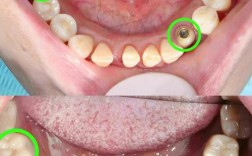

- 上牙可以做种植牙,技术成熟且效果良好。

- 上颌后牙区种植的主要挑战在于解决骨量不足(尤其是高度不足)的问题,常常需要配合上颌窦提升术。